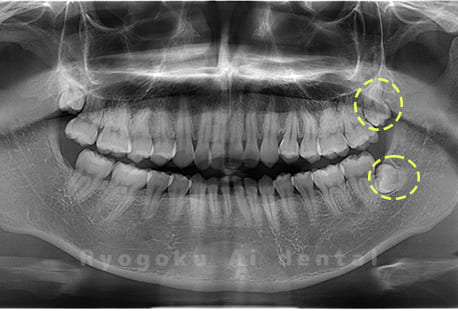

Case03

-

- 原因

- 上顎、下顎の親知らず

- 治療内容

- 上下4本の親知らずを抜歯したケースです。

<リスク・副作用>

手術後は痛み、腫れ、痺れなどの副作用が生じる場合があります。